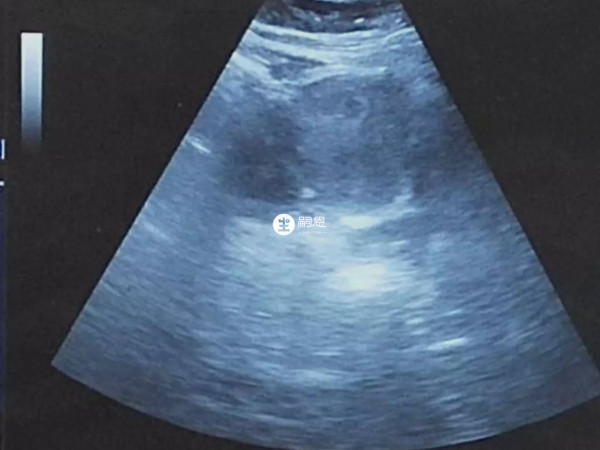

備孕一年多終於懷孕了,現在已經懷孕40天了,去醫院查了彩超,好多朋友看見我的B超圖都說是龍鳳胎。我第一次懷孕沒有經驗,所以想問下懷孕40天雙胞胎b超真實圖片是怎麼樣的?懷孕40天雙胞胎的真實B超影象上會顯示兩個孕囊和兩個胎心,這表明女性懷的是雙胞胎,可能是同性或異性雙胞胎。如果存在兩個孕囊,則通常是異卵雙胞胎。隨著妊娠時間的增加,會聽到兩個胎心,並觀察到兩個胎頭和胎臀。另外,懷龍鳳雙胞胎的孕婦查彩超,其B超檢查單可能會標註雙絨雙羊、單絨雙羊等資訊。

兩個寶寶助孕不同,有兩個胎心,在妊娠早期或晚期,雙胞胎的b超特徵與普通胎兒相似,只是在顯示胎兒外生殖器時會顯示男性生殖器和女性生殖器,兩個孕囊,異卵雙胞胎,可能是同性,也可能是雙生子,下面說說懷孕40天龍鳳雙胞胎真實b超圖片是什麼樣。